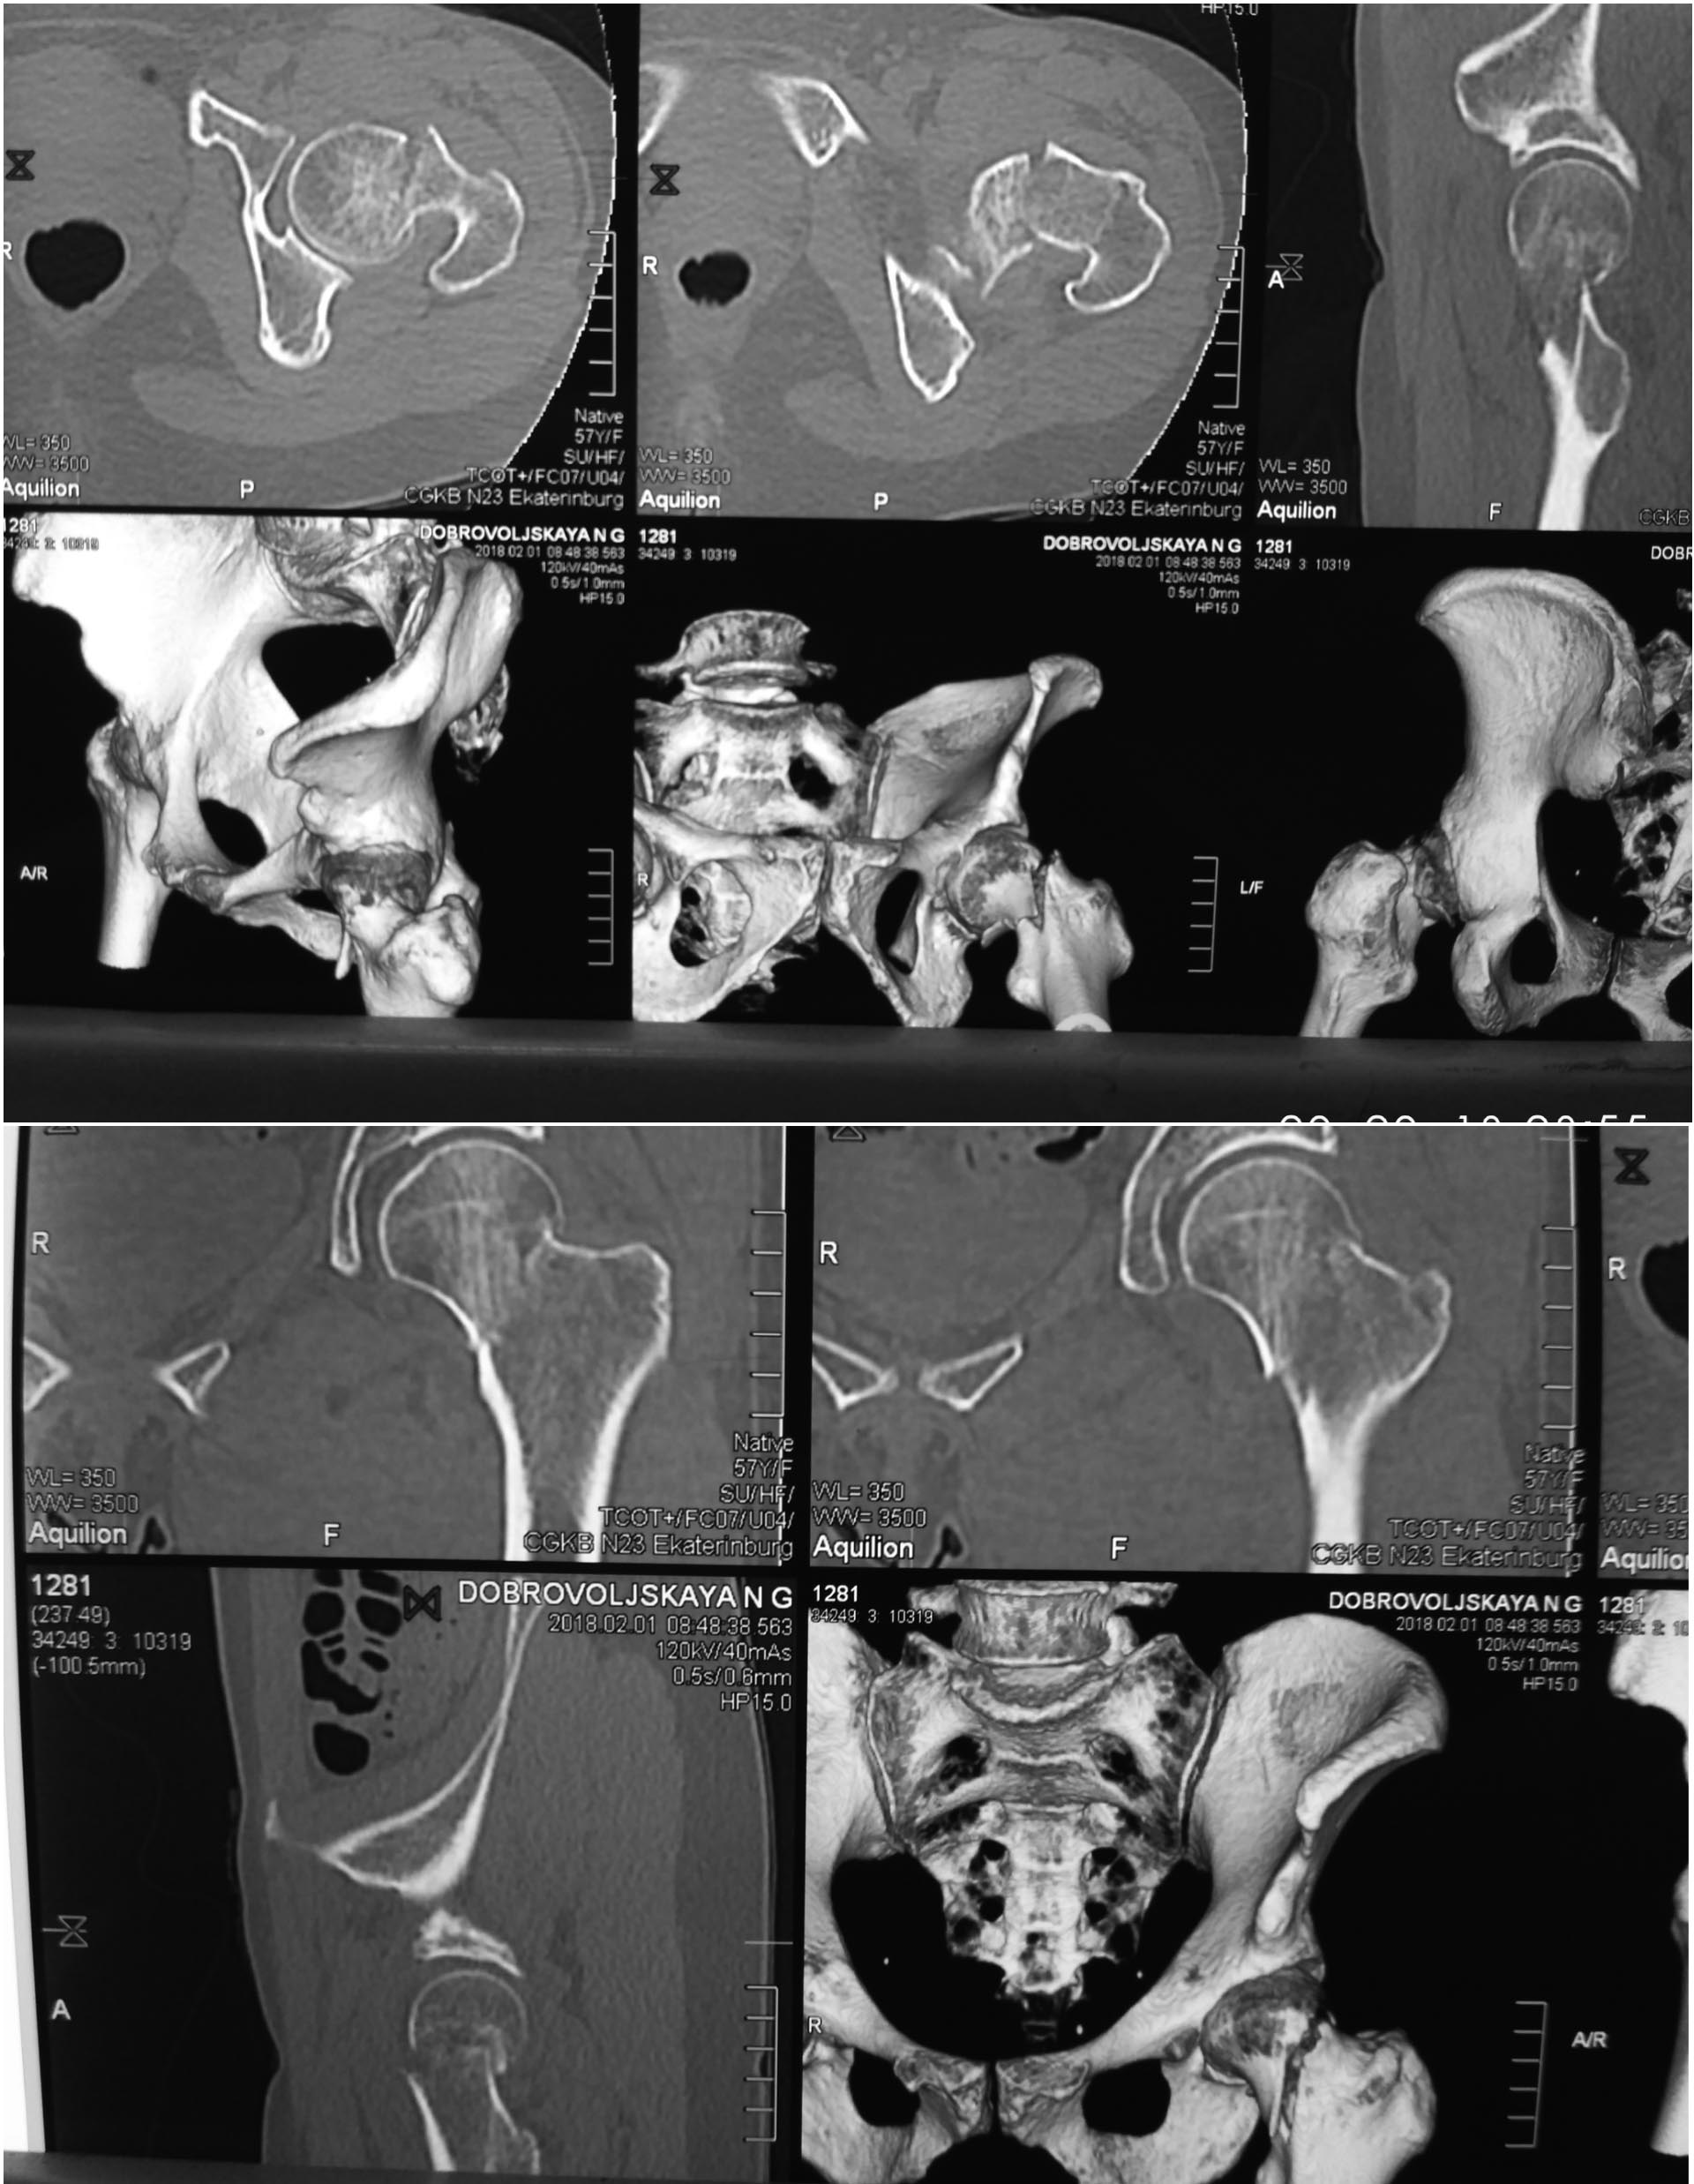

Пациентка ,57 лет ,сохранна ,активная. Травма низкой энергии. Помогите решить два вопроса - эндопротезирование или синтез?

Если синтез,то чем? (какой имплант , репозиоционные маневры ,открыто или закрыто)

Учитывая, что линия перелома имеет практически вертикальное направление (Павелс 2-3) будут преобладать силы скольжения поэтому как мне кажется лучше использовать PFN. Однако с учётом что перелом распространяется на головку а сустав имеет признаки дисплазии а также возраст с сроки с момента травмы я бы предпочтение отдал тотальному эндопротезированию

Учитывая линию перелома, если делать остеосинтез то сразу же с вальгизирующей остеотомией, без этого шансы на сращение призрачные. Фиксировать либо клинковой прастиной, или штифтом. В 57 лет, ещё можно попытаться сохранить головку.